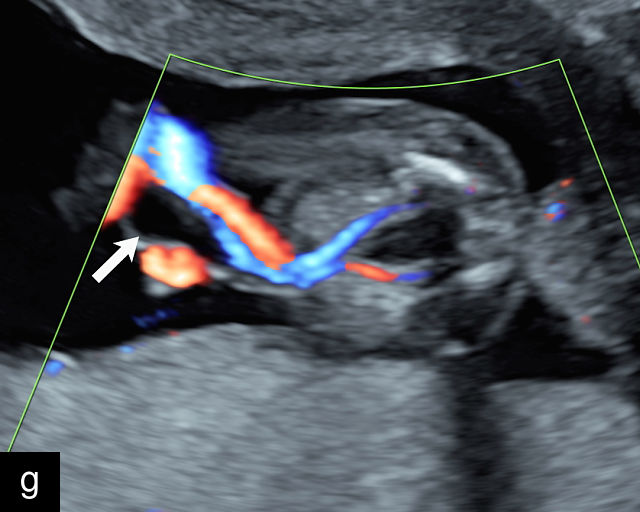

21

(a) Type-1 vasa previa. Photograph after delivery showing the umbilical cord inserting into the membranes through which unprotected fetal vessels run to insert into the placental edge. (b) Type-2 vasa previa. Photograph after delivery showing bilobed placenta with unprotected fetal vessels running though the membranes between the lobes. (c) Type-3 vasa previa in a twin pregnancy. Photograph after delivery showing unprotected vessels running through the membranes from one edge of the placenta to another (arrow). (d) Transabdominal grayscale ultrasound of the lower uterine segment showing a linear hypoechoic structure (fetal vessel) running over the cervix (c) indicating vasa previa (Type 2). b, bladder; h, fetal head. (e) Transabdominal color Doppler ultrasound of the lower uterine segment showing fetal vessels (arrow) running over the cervix (c) indicating vasa previa (Type 2). (f) Transabdominal ultrasound with color flow and pulsed-wave Doppler of the lower uterine segment showing a fetal vessel running over the cervix (c) indicating vasa previa (Type 2). Pulsed-wave Doppler demonstrates an umbilical arterial waveform. (g) Transvaginal grayscale ultrasound with showing a Type-2 vasa previa. There are two placental lobes, an anterior (a) and a posterior (p) lobe. There is a linear and circular hypoechoic structure (arrow) running over the cervix (c) between the lobes. (h) Transvaginal grayscale ultrasound image of vasa previa. A hypoechoic linear structure (arrow) is seen running through the membranes over the cervix (c). h, fetal head. (i) Transvaginal grayscale ultrasound of vasa previa. Hypoechoic circular and linear structures are seen close to the internal os. (j) Transvaginal color Doppler ultrasound image of vasa previa. A fetal vessel is seen running through the membranes over the internal os (arrow) of the cervix (c). h, fetal head. (k) Transvaginal ultrasound with color Doppler showing a Type-2 vasa previa. There are two placental lobes, an anterior and posterior lobe (pl). Fetal vessels run over the cervix between the lobes. (l) Transvaginal color flow ultrasound with pulsed-wave Doppler image of vasa previa. Color Doppler shows flow through the vessel and pulsed-wave Doppler shows a fetal umbilical venous waveform. (m) Transvaginal color ultrasound with pulsed-wave Doppler image of vasa previa. Color flow Doppler shows flow through the vessel and pulsed-wave Doppler shows a fetal umbilical arterial waveform. (n) Transvaginal three-dimensional ultrasound with color Doppler image of vasa previa. h, fetal head; c, cervix.

12